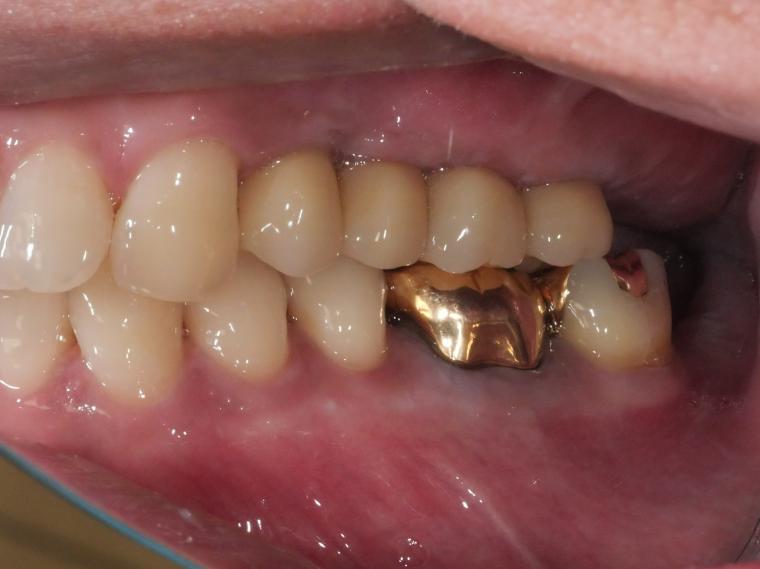

上顎臼歯部欠損症例

BEFORE

41歳男性/上5本欠損/インプラント埋込手術

上5本が虫歯になってしまった為治療をすることになった患者さんです。

虫歯が進行していて、歯を保存出来なかったため歯を抜いて人工の骨を足してからインプラントを

5本埋込した患者さんです。